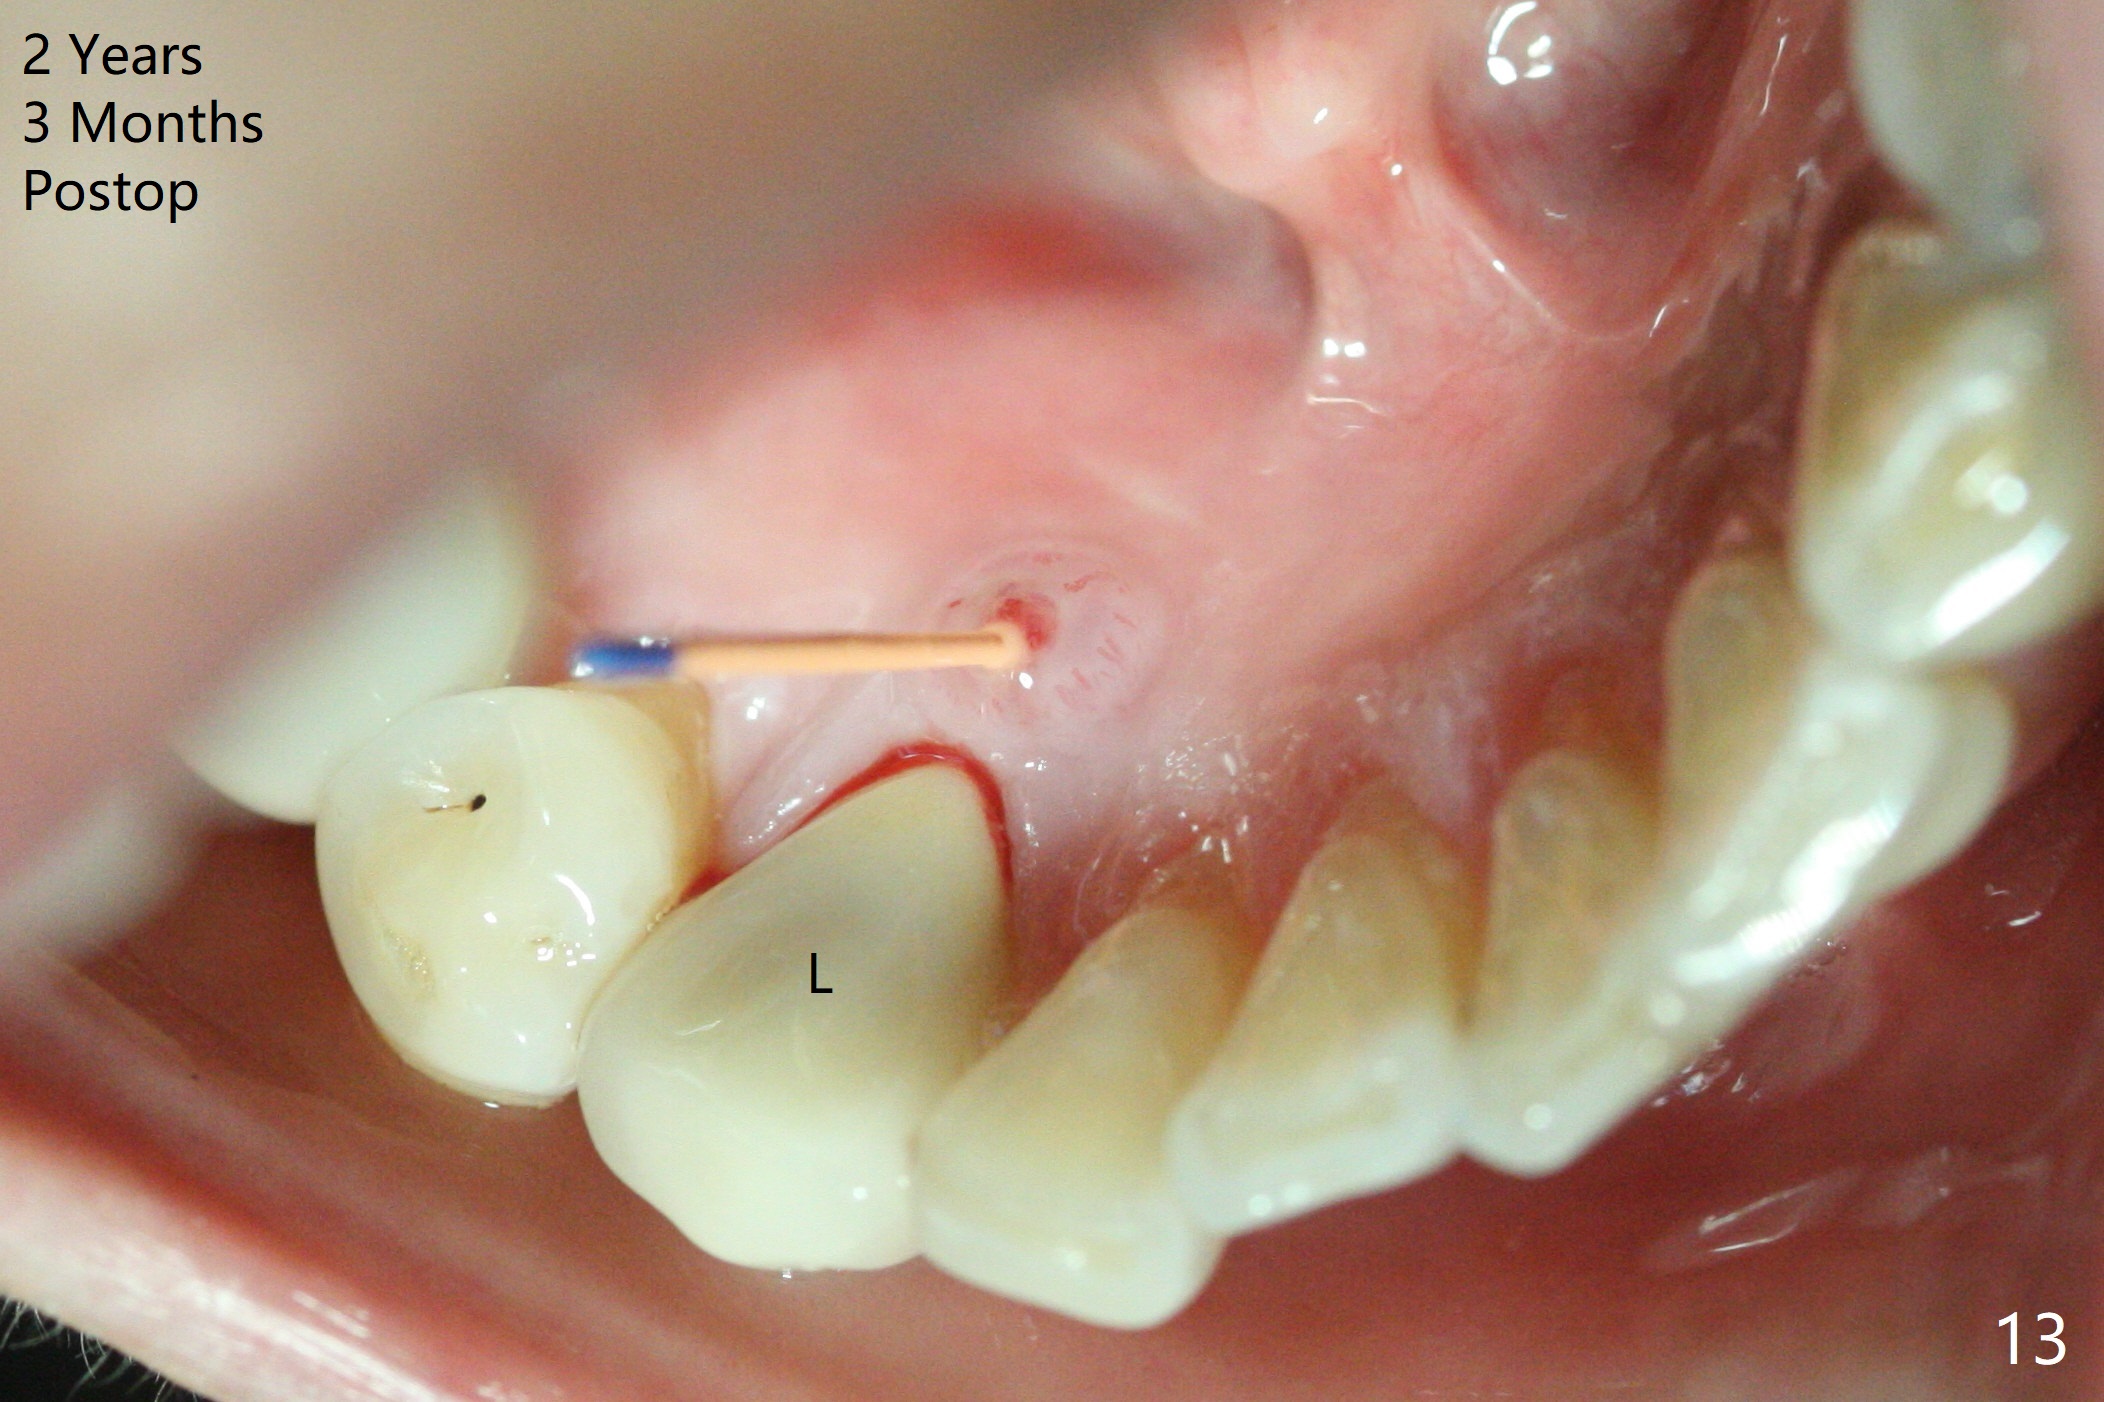

The patient reports that the fistula disappears after initial RCT at #27, but it seems to re-appear 1 month post canal debridement (Fig.5 >). After repeated debridement with #40 hand file at 23 mm, apply Endo Sequence BioCeramic Sealer and insert GT 40/.08 master cone with black carrier (Fig.6). One hour later, the patient returns with re-appearance of the fistula (Fig.7). Following local anesthesia, poking the fistula leads to sealer escape (Fig.8). After debridement of the fistula until the bone, PA is retaken (Fig.9). A crown was made in China; mesial radiolucency starts (Fig.10). The tooth remains asymptomatic 1 year 5 months postop (Fig.11). There is a lingual fistula with enlarged mesial radiolucency 2 years 3 months postop (Fig.12-14).